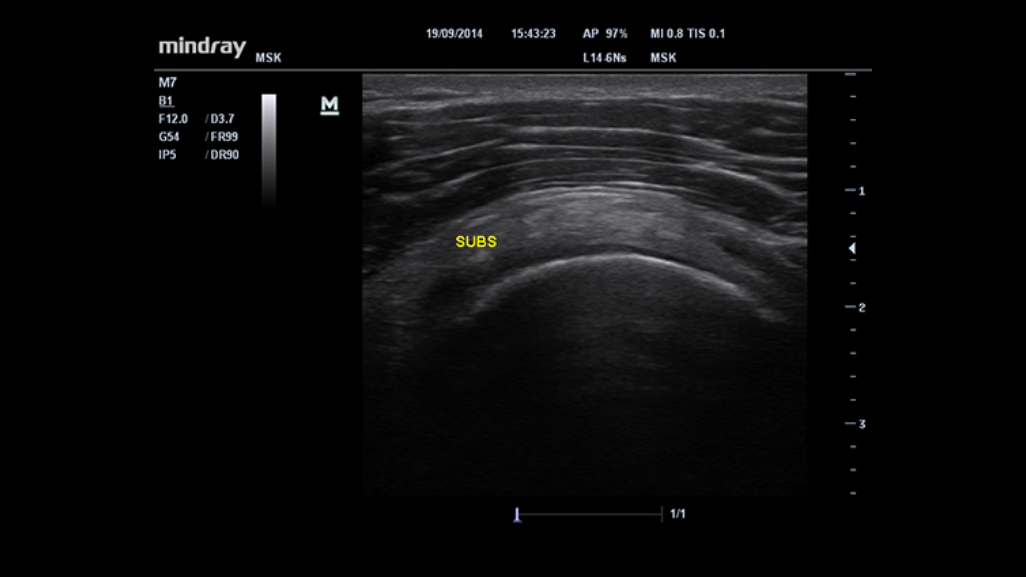

Smart Track

Due to the new platform, the smart track enables to automatically optimize color box and Doppler gate placement accurately, making sure the optimal and best display for color flow and spectral Doppler signal.